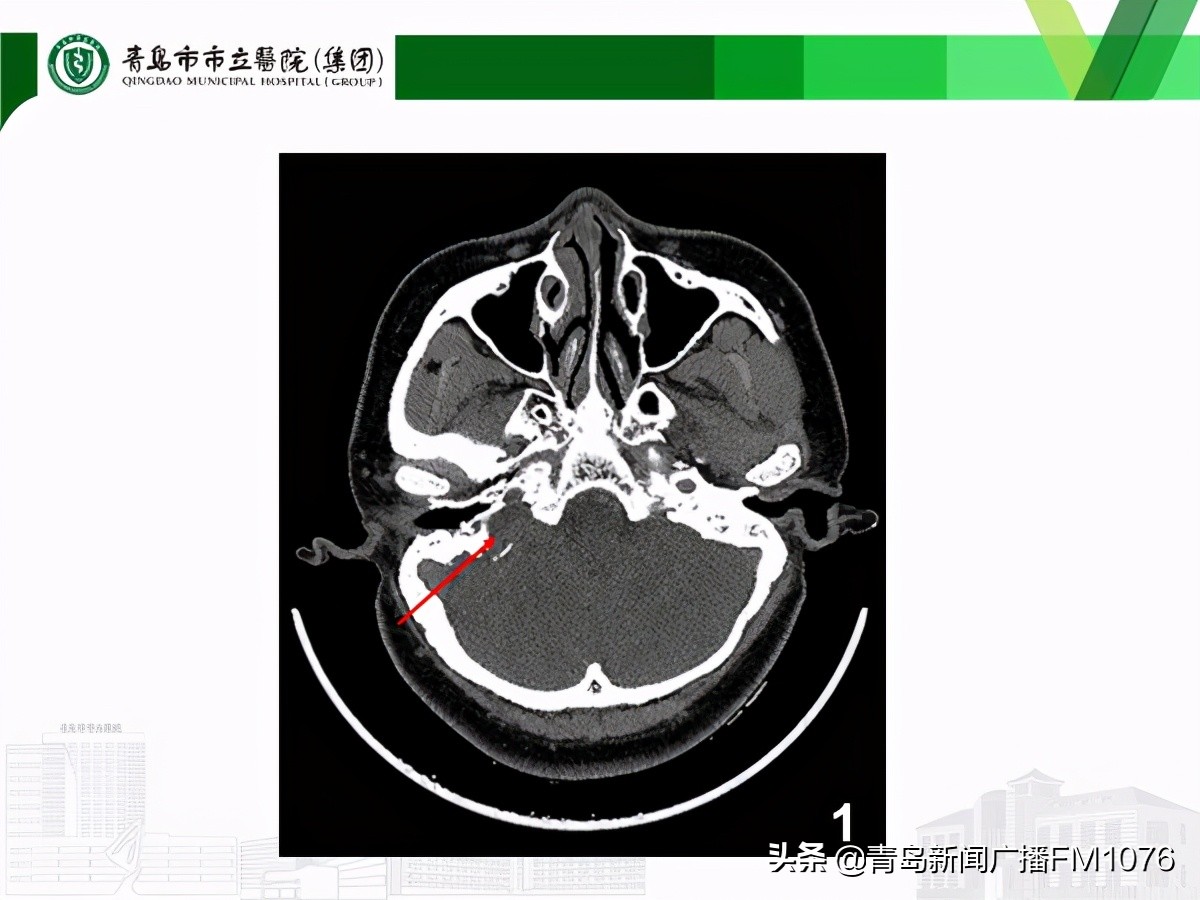

患者的病变位于右侧颈静脉孔区-颞骨岩尖部-后颅窝部,有一块很大的不规则软组织影,周围骨质已经出现破坏,病变周围密布着颈内动脉、乙状窦、颈内静脉、面神经。李主任非常清楚,这是一颗十分“狡猾”的肿瘤,不仅位置深在,而且它周围布满神经血管,稍有不慎,便会给患者造成更大的伤害。患者已出现面部抽搐,表明肿瘤已经刺激到面神经,如不尽快手术,肿瘤会不断增长,患者将会出现面瘫、颅内感染等更严重症状。

肿瘤周围相关的神经血管结构示意图